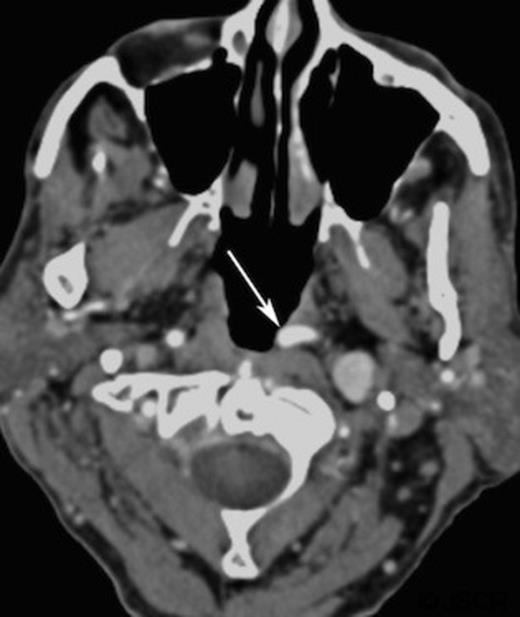

A CT scan, requested as part of his lymphoma follow-up, revealed asymmetrical fullness of the left nasopharynx due to a mass in the retropharyngeal space.(Figure 1) Owning to patient intolerance, nasoendoscopy was difficult in the clinic setting, and the nature of this swelling could not be properly determined. With the history of previous malignant disease, and the risk of recurrence or new disease being high, a biopsy was requested by the oncology team. However, since the CT imaging showed that the bulging mass could possibly be an artefact of a medially coursing left internal carotid artery (ICA), it was decided to perform a magnetic resonance imaging (MRI) prior to the biopsy. The MRI confirmed the ICA ectasia (often referred to as tonsillar loop) which manifested the asymmetry of the contour of the nasopharynx with prominence and fullness on the left just below the fossa of Rosenmuller.(Figure 2) There was no evidence of any mucosal abnormalities of nasopharynx or of the remainder of upper aerodigestive tract. No other pathological lesion was noted and the biopsy was cancelled.

Contrast enhanced axial computed tomography of parapharyngeal region showing left retropharyngeal mass (arrow)